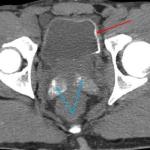

Cystite emphysémateuse

Une patiente de 89 ans, sans antécédent majeur, consulte aux urgences à la suite d’une chute accidentelle avec fracture...